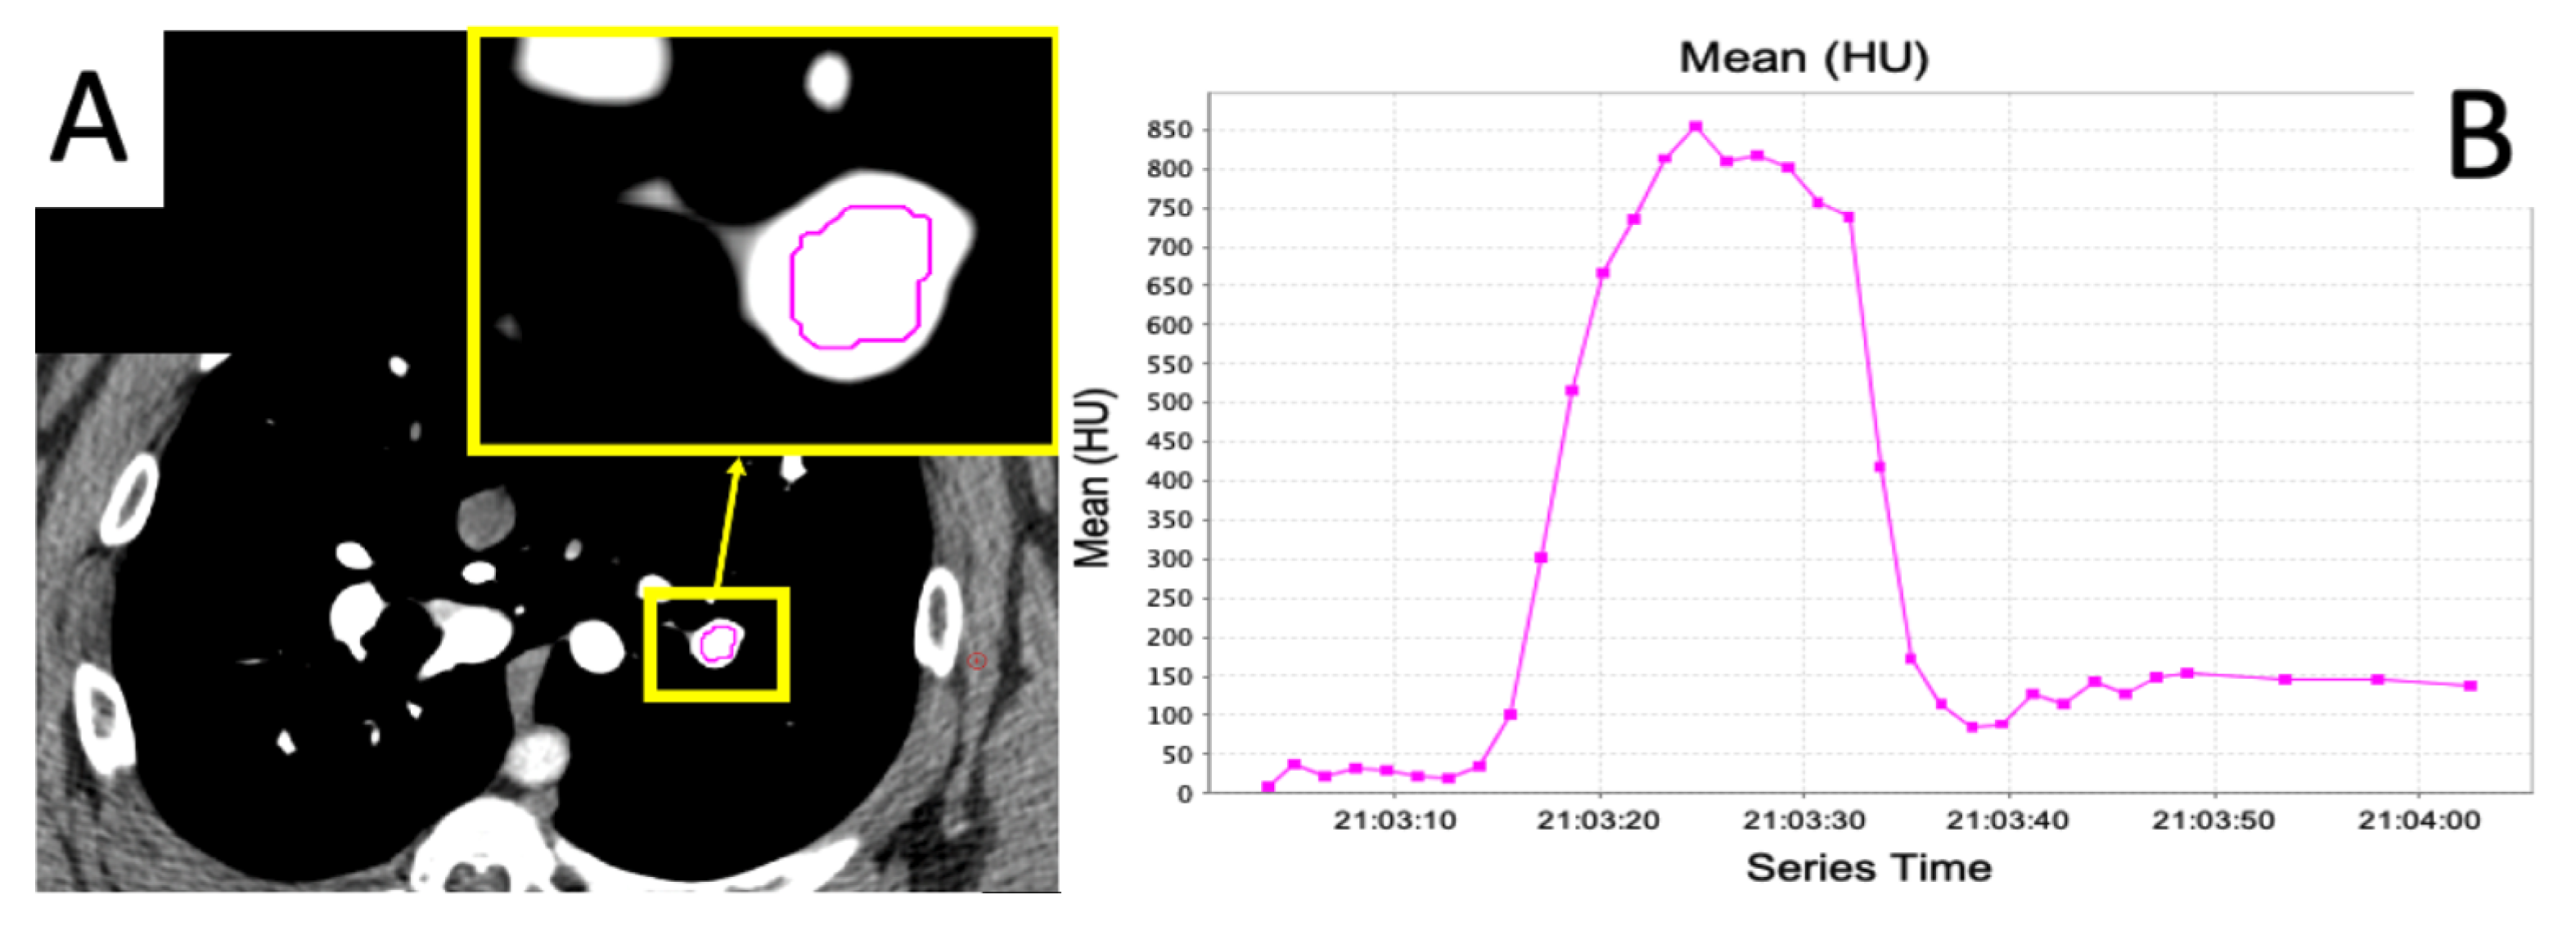

2.4. Dynamic Contrast CT

2.5. Regional Perfusion Analysis

Imaging Results